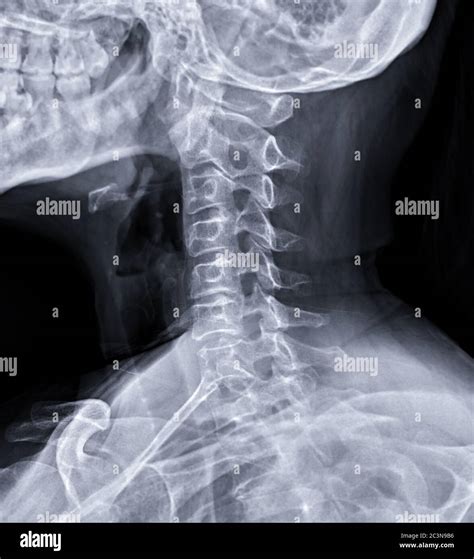

Medical imaging plays a crucial role in modern diagnostics, providing physicians with a detailed look inside the human body without the need for invasive procedures. Among the various techniques used to capture the most accurate images, patient positioning is paramount. One essential position utilized extensively in fluoroscopy, X-rays, and cardiac imaging is the Right Anterior Oblique (RAO) view. Understanding this specific orientation is fundamental for radiographers and clinicians alike, as it allows for the clear visualization of anatomical structures that might otherwise be obscured in standard frontal views.

The Right Anterior Oblique (RAO) position is a specialized radiographic projection. In this setup, the patient is positioned so that their right anterior chest wall is closest to the image receptor (the film or digital detector). The body is rotated at a specific angle—typically between 45 and 60 degrees depending on the specific anatomy being studied—away from the true posteroanterior (PA) position.

By rotating the patient to the right, the radiologist can "open up" areas that overlap in standard projections. For example, in cardiac imaging, the RAO view is frequently used to visualize the coronary arteries, the left ventricle, and the outflow tract of the heart without the shadow of the spine interfering with the clarity of the images.